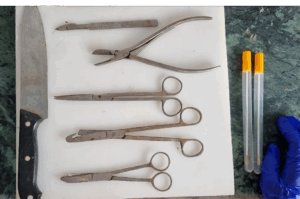

Equipment for postmortem (Fig.1):

- Small and large straight scissors with pointed as well as blunt ends.

- Curved scissors.

- Small and large knives.

- Scalpel or blade.

- Bone cutter and a saw.

- Small and large forceps.

- Tooth forceps.

- Hand lens.

- Hand gloves – rubber or latex.

- Bunsen burner or spirit lamp or stove.

- Syringes and needles.

- Spirit or alcohol.

- Cotton and cotton swabs. Sterile swabs, vials, petri dishes and test tubes. (swab for bacteria and virus are different)

- Pasteur pipettes and rubber bulbs.

- Fixatives like 10% formalin, formol saline or netural formalin.

- Clean glass slides and coverslips.

- Different staining sets and stains like Gram’s, Ziehl – Neelsen, Giemsa and Wright’s stain.

- Normal saline and glycerine saline.

- Small and large trays.

- Matches and torch.

- Disinfectants like dettol, savlon, phenol etc.

- Insecticides or electric flytrap for controlling fly population.

Figure 1. Post mortem equipment/materials